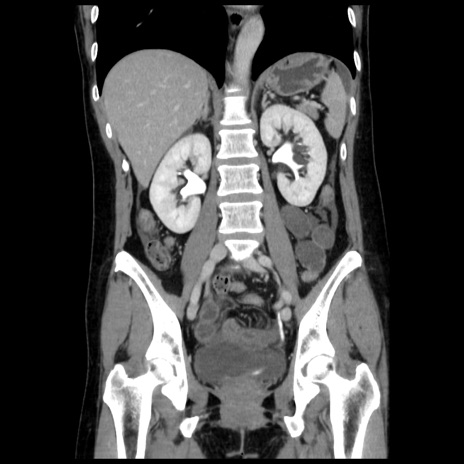

症例10(冠状断像)

【症例】 50歳代女性

【主訴】 腹痛

【現病歴】前日生レバーを食べた。今朝に排便あり。 昼前に突然発症の腹痛を生じ、当院救急外来を受診した。

【既往歴】 子宮筋腫にてで子宮全摘後

【身体所見】 意識清明、腹部:平坦、軟、下腹部やや左を中心に圧痛・反跳痛あり、筋性防御あり

【データ】WBC 7800、CRP 0.07